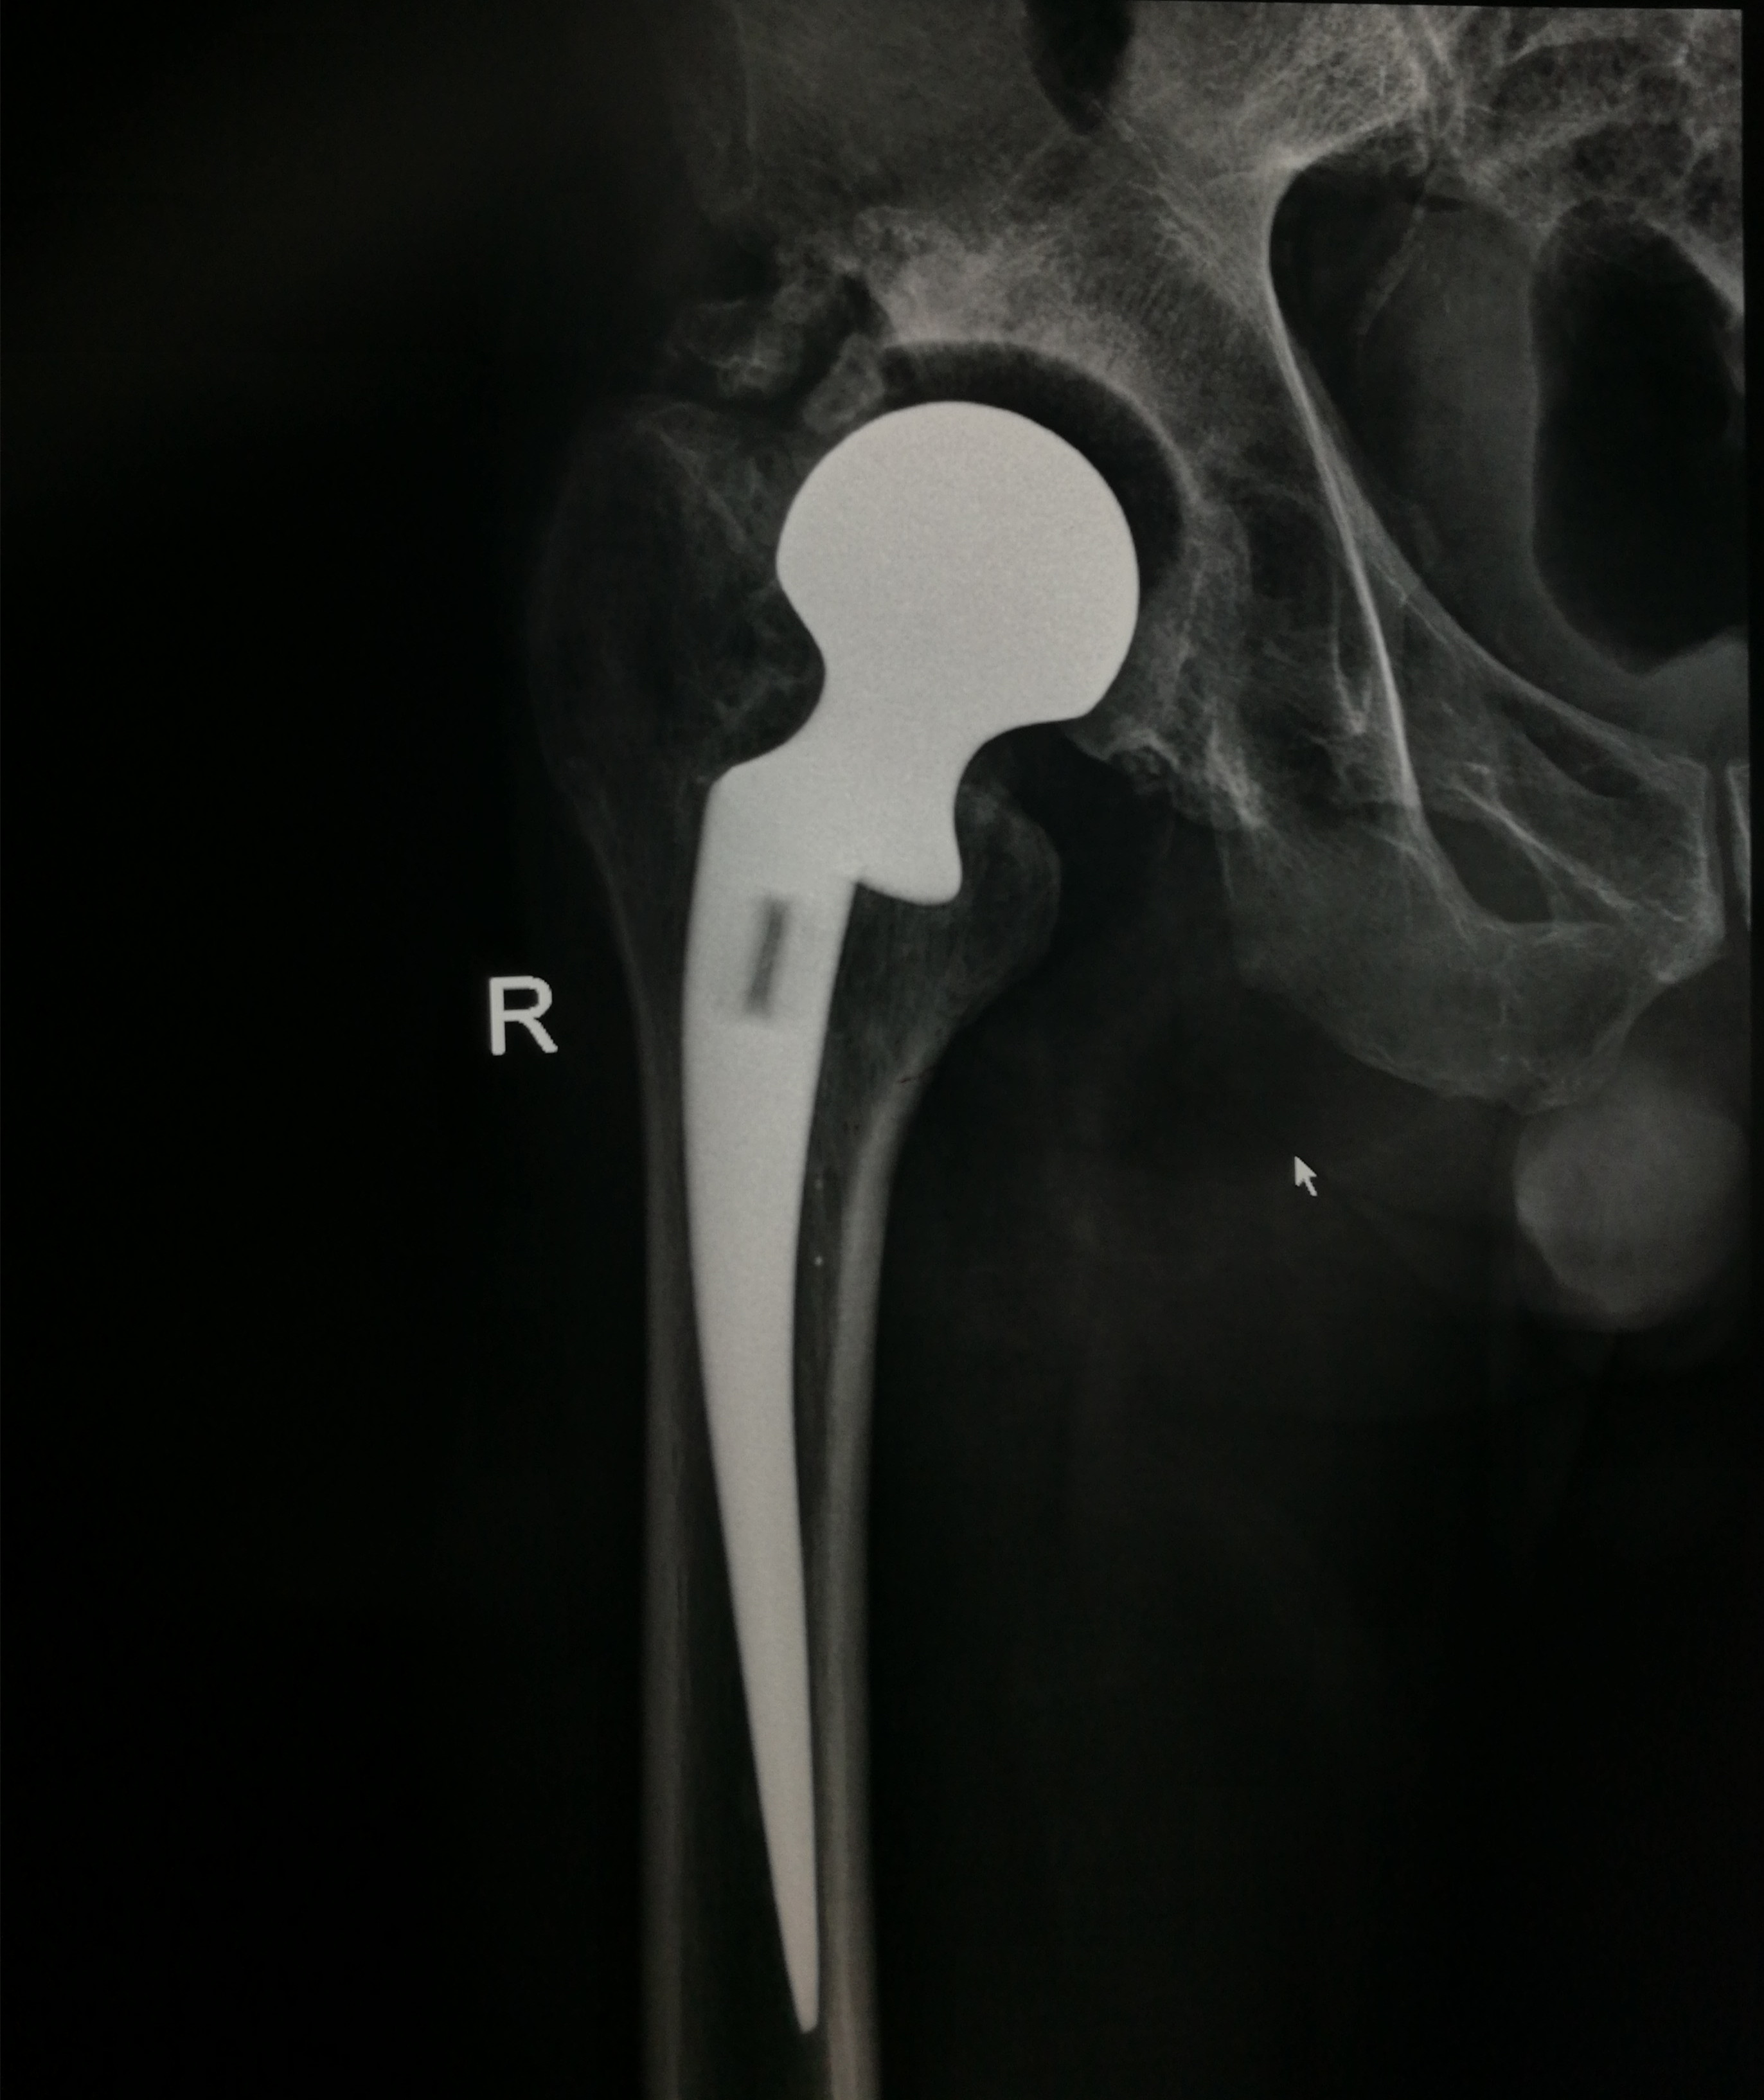

手术于腰硬联合麻醉下进行,刘主任联合手术医师另行切口,采用钢丝捆绑的方法取出原来关节假体,并重新磋磨髓腔、髋臼,安放新的髋臼假体;随后用骨水泥固定股骨柄假体,并在股骨大转子外侧壁的劈裂骨槽处用接骨板复位坚实固定。术中克服种种不利因素,用时近4个小时,顺利完成右侧髋关节翻修。

术后,刘主任及时为患者量身制定了功能康复锻炼方案,在骨一科医护人员的精心指导下,王先生右下肢功能逐渐恢复。X线检查示:右髋部假体位置良好,力线良好;经术后测量右下肢较左下肢长度相差1cm,基本恢复双下肢等长。术后14天,王先生已能够拄拐下地行走,并顺利拆线出院。该手术的成功标志着我院骨一科在我县骨科临床技术领域获得质的突破。